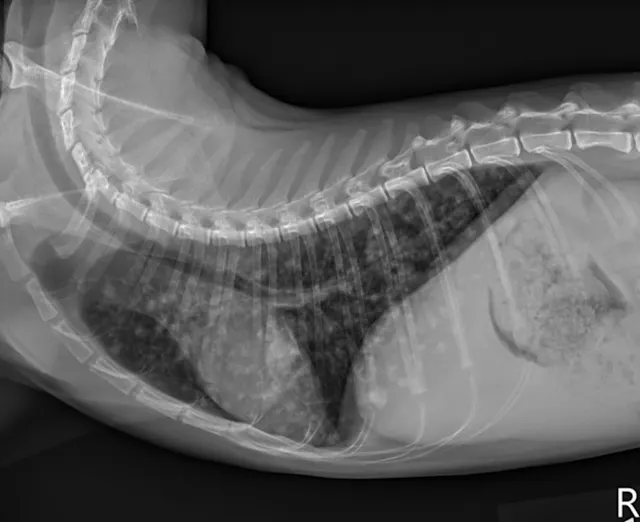

At the 2-month recheck, continued clinical improvement was observed. The owner reported Eleanor was doing well at home. Her body weight had increased to 8.3 lb (3.8 kg); BCS was 4/9.On physical examination, mildly increased bronchovesicular sounds were still present. Fundic examination results were normal. Thoracic radiographs showed continued improvement; remaining lesions were predominantly in the peripheral lung field with a more caudodorsal distribution (Figure 3).

FIGURE 3 Left lateral (A), right lateral (B), and ventrodorsal (C) thoracic radiographs 2 months after initiation of itraconazole. Remaining lesions (arrows) were predominantly in the peripheral lung field with a more caudodorsal distribution.